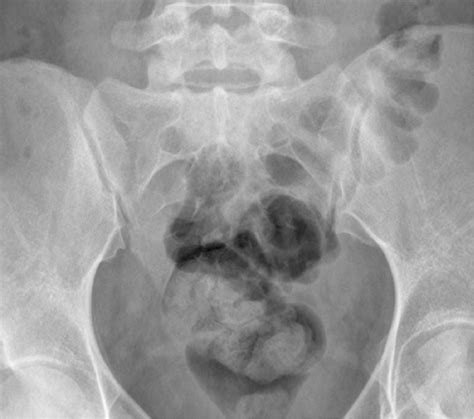

• Detecting Bone Abnormalities: Identifying fractures, tumors, or significant structural anomalies.

• Evaluating Degenerative Changes: Assessing for signs of osteoarthritis, such as joint space narrowing or bone spurs (osteophytes).

• Identifying Ankylosing Spondylitis: Looking for characteristic signs like erosions or fusion of the joint, which are common indicators of this inflammatory condition.

• Joint Space Width: A narrowing of the joint space often indicates wear and tear or degenerative joint disease.

• Sclerosis: This refers to an increase in bone density around the joint, which is a common response to chronic stress or inflammation.

• Erosions: Small "nibbles" in the bone surface, which are highly suggestive of inflammatory arthritis.

• Ankylosis: The fusion of the joint, where the space between the bones has disappeared entirely.